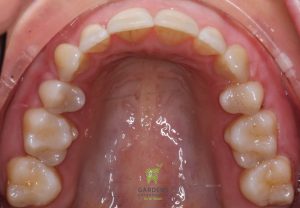

Impacted upper right Canine with space opening and guided eruption

Initial and Final Panoramic X-rays showing an impacted canine (upper right) erupted in place